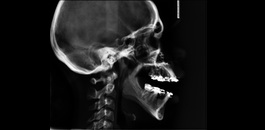

Teleradiografia lateral de perfil

Indicada para realização de análises cefalométricas. Sendo possível a avaliação das estruturas ósseas e respectivas interrelações. Muito indicada para planejamentos ortodônticos e ortopédicos.